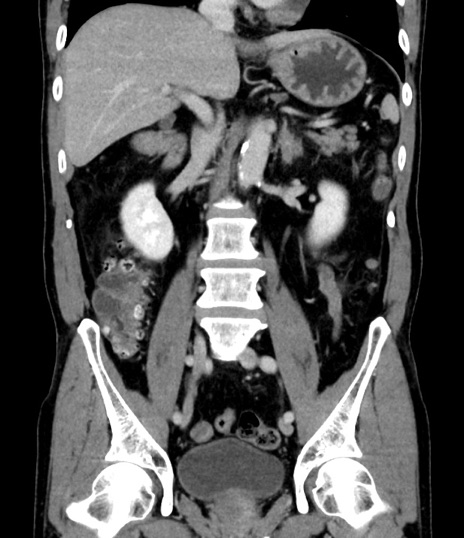

症例8(冠状断像)

【症例】 60歳代男性

【主訴】 黒色吐物

【現病歴】 4日前から嘔気自覚、2日前の朝食後にも嘔気あり、自分で手で嘔吐反射起こし嘔吐したところ血が混ざっていたため受診。

【既往歴】 5年前汎発性腹膜炎を伴う急性虫垂炎で手術、高血圧、前立腺肥大症、高脂血症

【身体所見】 腹部正中に手術癩痕あり 腹部平坦・軟圧痛なし膨満感あり

【データ】WBC 8400、CRP 4.54